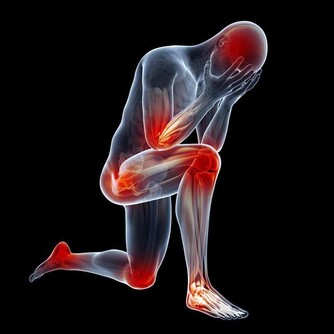

1、阿司匹林

阿司匹林是個神藥,是很多心腦血管疾病的患者離不開的藥,對於很多冠心病病人,醫生都會建議每天服用阿司匹林100mg,但是有證據顯示,當每天服用阿司匹林30-100mg時,可能會抑制腎臟代謝尿酸。

2、利尿劑

利尿劑能夠致使痛風發作其實很好理解,利尿後外周循環血容量降低,腎小球濾過率降低,代償性的近曲小管重吸收作用增加,可能使得尿酸排泄減少,在臨床上能遇到很多痛風患者,長時間沒有發病,因為服用了利尿劑後致使痛風再犯。